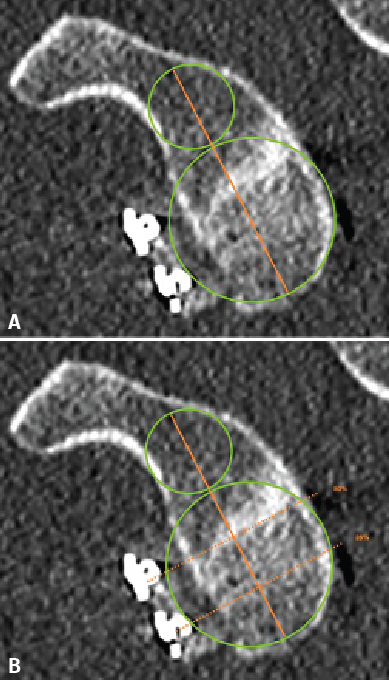

Figure 2. Evaluation of graft positioning in the sagittal section. Two lines are traced of a length equivalent to the size of the glenoid bone defect (B) and to the length of the graft covering the defect (A). Image A shows how most of the bone defect is covered by the graft - the latter therefore being considered to be well positioned. Image B shows that less than 90% of the bone defect is covered by the graft - the latter therefore being considered to be inadequately positioned.

Taking the posteroinferior glenoid border as reference, we traced a first circumference over its contour, and a second circumference above the previous one and tangential to the glenoid borders. The line joining the centre of both circumferences was taken to represent the axis of the glenoid cavity. Over this we estimated the point corresponding to the half and 25% of the glenoid height (Figure 1). The sagittal section was used to determine the position of the graft in the craniocaudal direction (Figure 2). The length (in mm) of the bone defect was measured (B), along with the amount of bone graft covering the defect (A). Percentage covering of the bone defect was estimated from the ratio between A and B. The graft was considered to be well positioned when the percentage coverage of the defect was at least 90%.

Figure 3. Evaluation of the graft position in the axial view, according to the description of Kany et al.(14). A circumference is traced over the glenoid border, and following the curvature of the latter, the amount of graft (in mm) extending beyond or failing to reach this line is measured. Image A shows the graft perfectly positioned, following the curvature of the glenoid concavity. Image B shows the graft medial with respect to the line. Image C shows the graft positioned too lateral.

The position of the graft in the mediolateral direction was evaluated in the axial sections corresponding to 50% and 25% of the glenoid height. For this purpose we used the curvature method described by Kany et al.(14); on the glenoid border and following its curvature, a circumference was traced and we quantified (in mm) the amount of defect that did not reach or surpassed that line at the point where the graft was closest to the native glenoid cavity (Figure 3). Optimum positioning of the graft was considered when the latter was located in line with the glenoid cavity, up to 3 mm lateral or up to 5 mm medial with respect to the glenoid joint border(14). Grafts protruding more than 3 mm were considered to be located lateral, while those located more than 5 mm medial to the glenoid joint surface were classified as being medial.